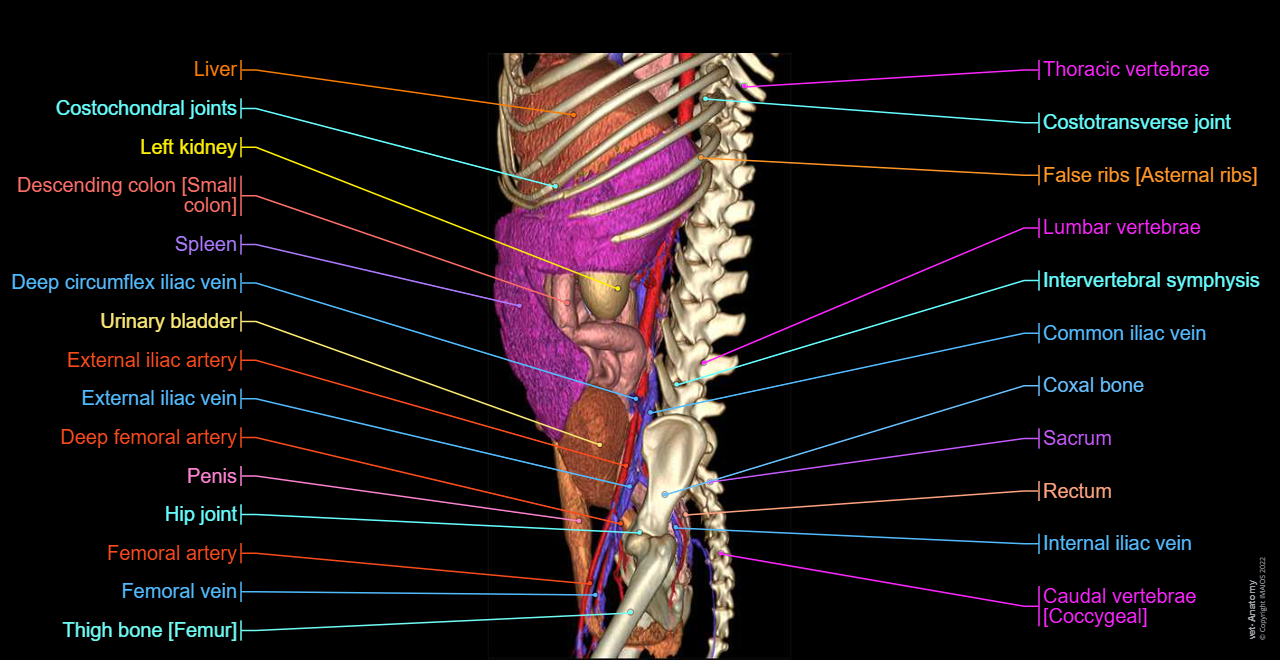

Dog - Osteology:3D - Bones - Anatomical pictures

Dog - 3D - Urogenital system: Penis, Penile bone [Baculum], Urinary bladder, Male urethra, Male genital organs

Dog - Abdominal aorta - Anatomy - 3D: Celiac artery, Splenic artery, Hepatic artery, Cranial mesenteric artery, Caudal gluteal artery, Internal pudendal artery

Veterinary anatomy - 3D: Dog - Splanchnology - Abdominal cavity